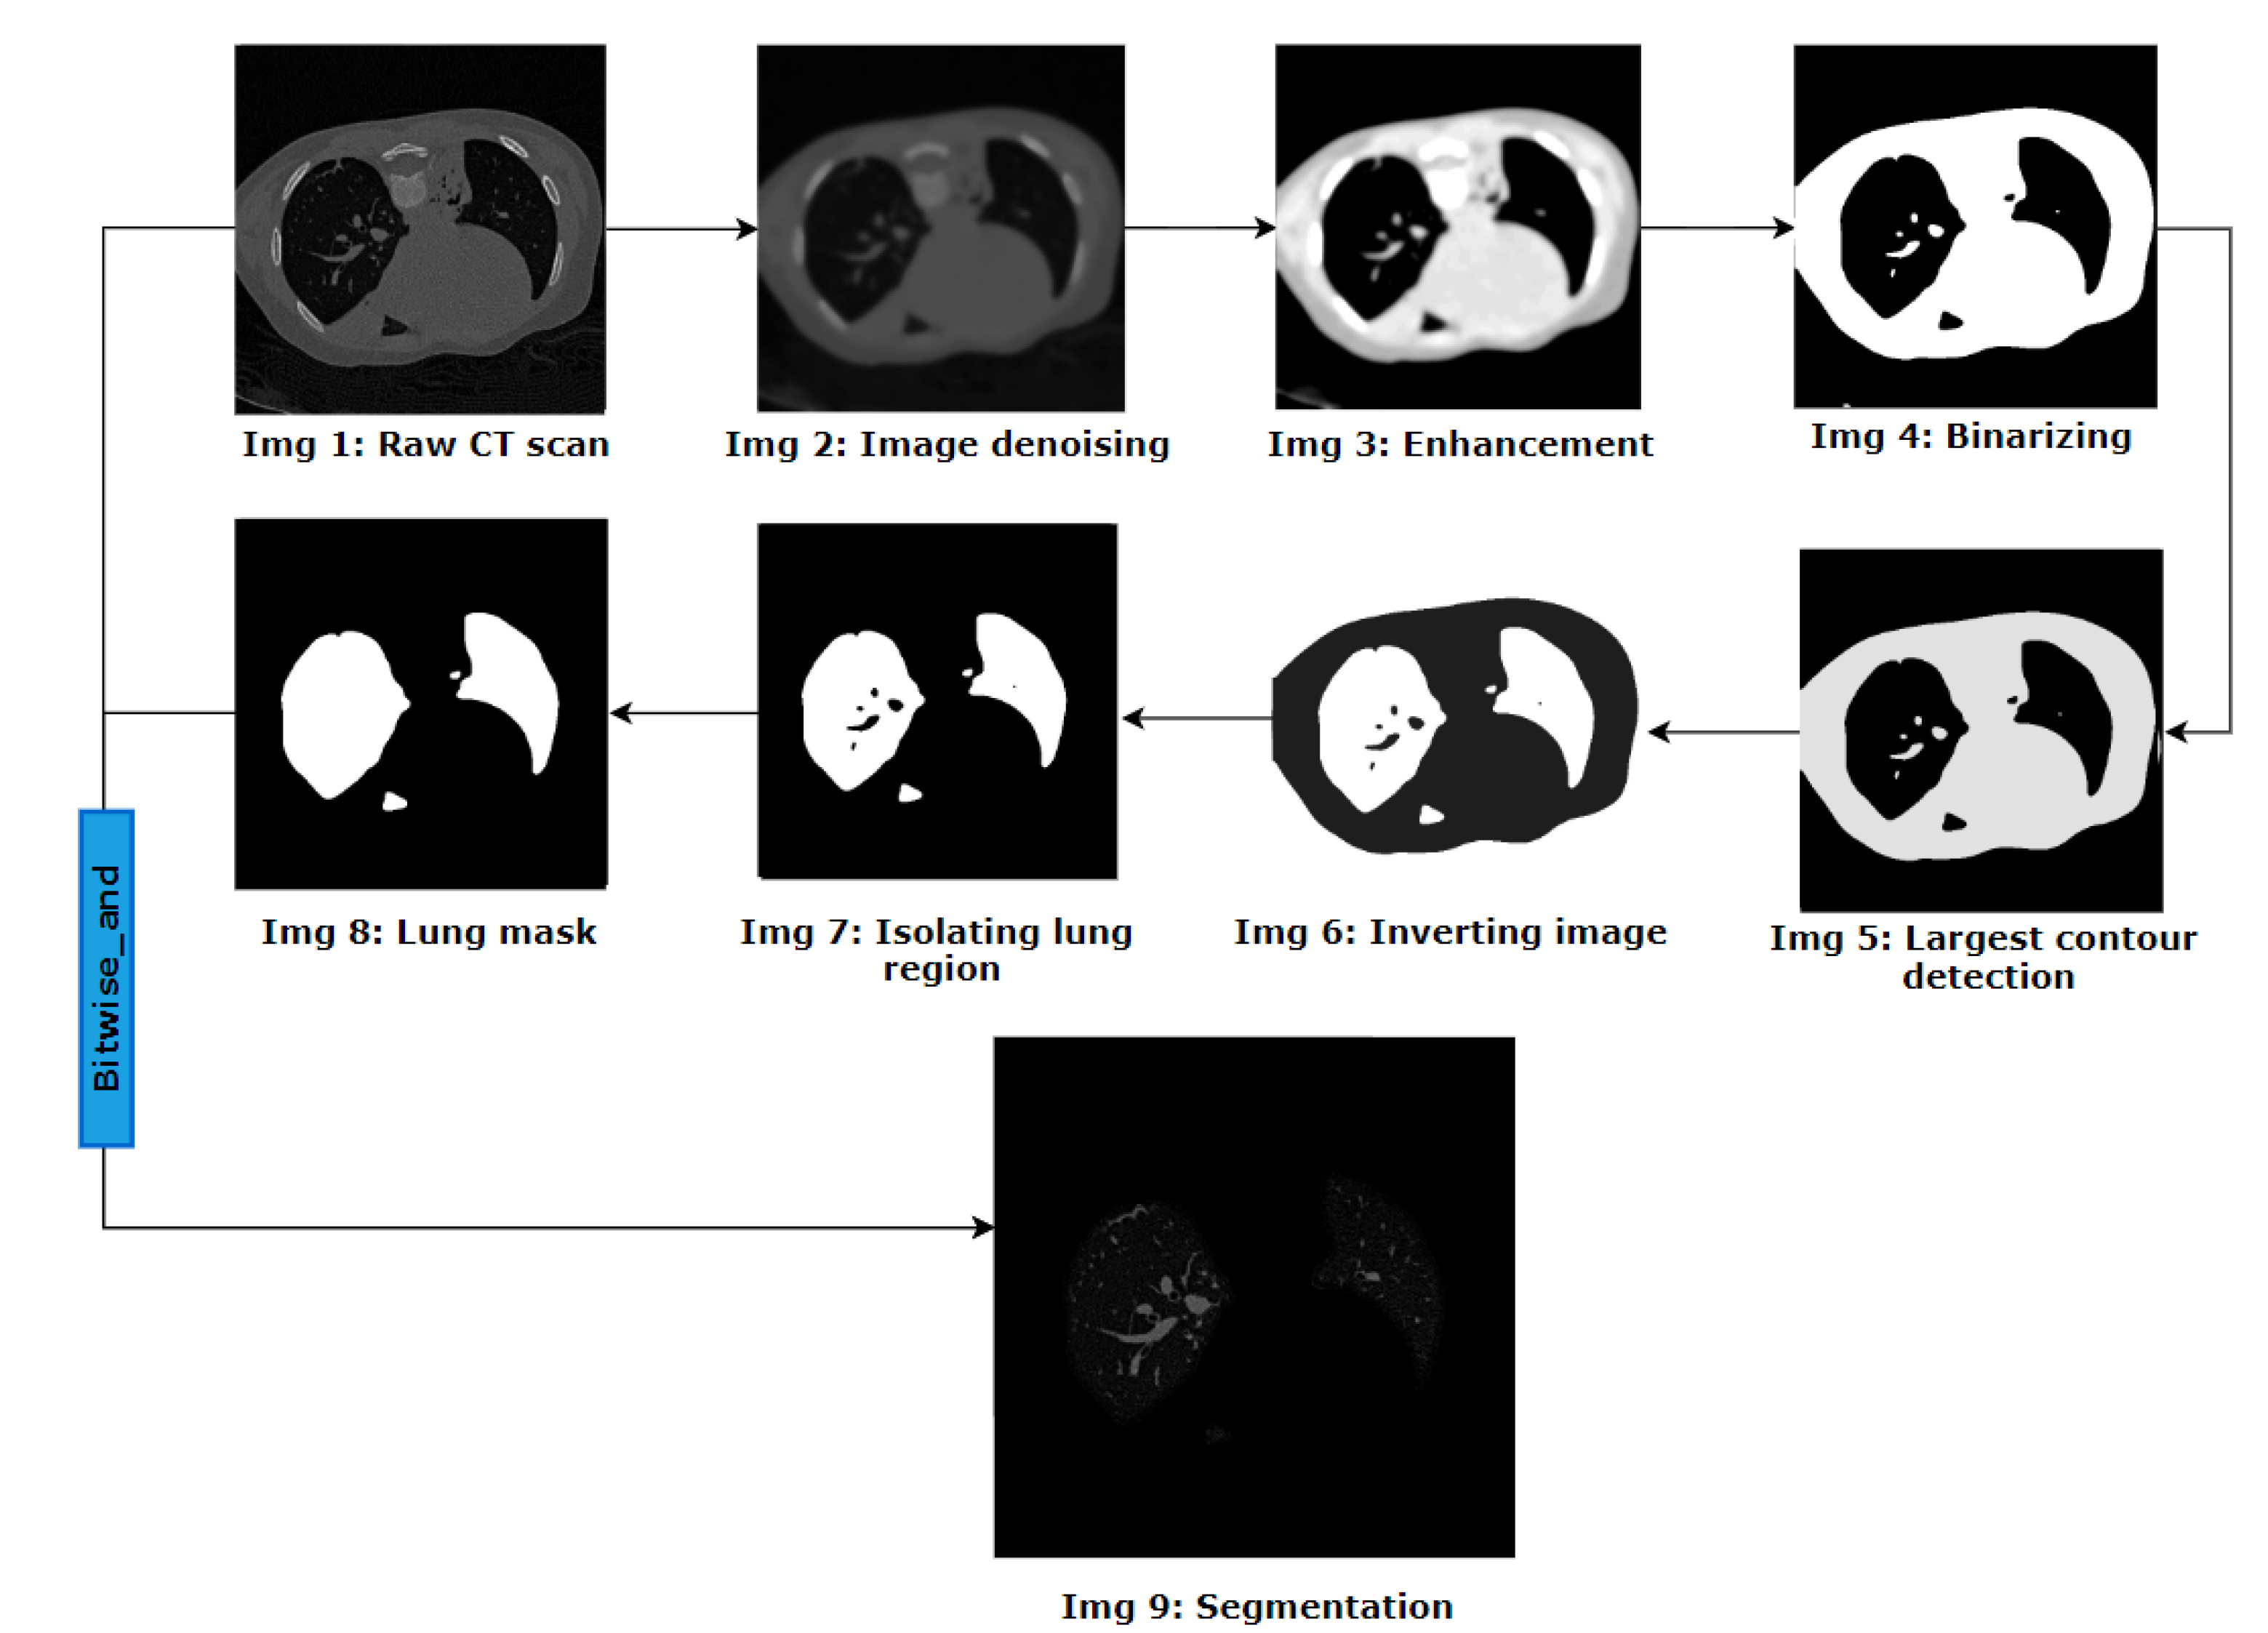

- To identify BA pairs, lung segmentation and image cleaning are conducted using several image preprocessing and custom-developed algorithms.

3.1. Lung Segmentation